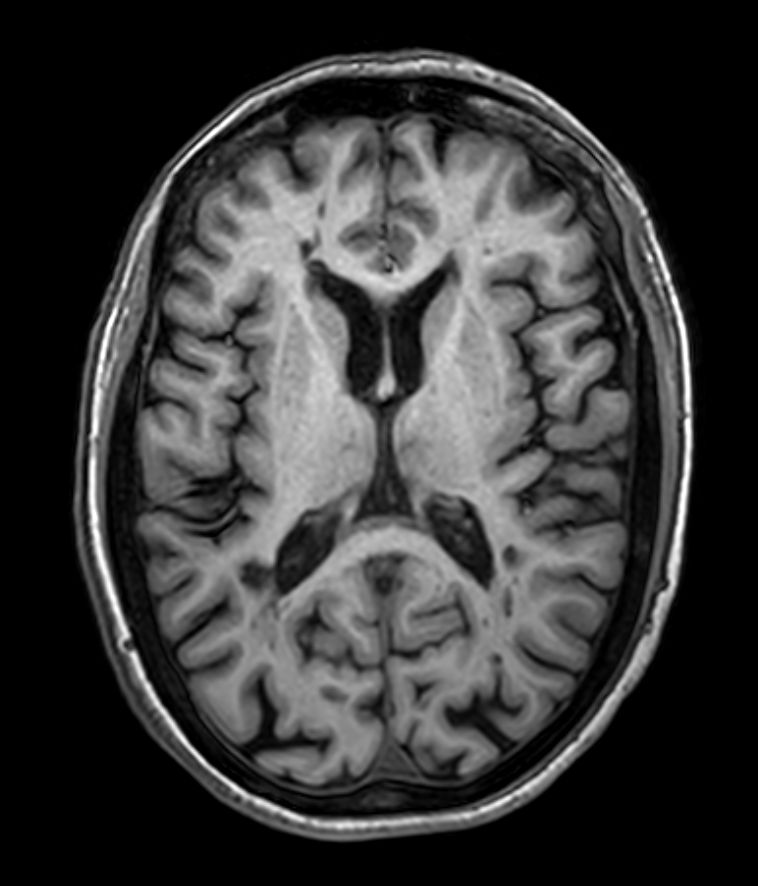

3D T1w FFE Compressed SENSE

3D T1w FFE (reformat) Compressed SENSE